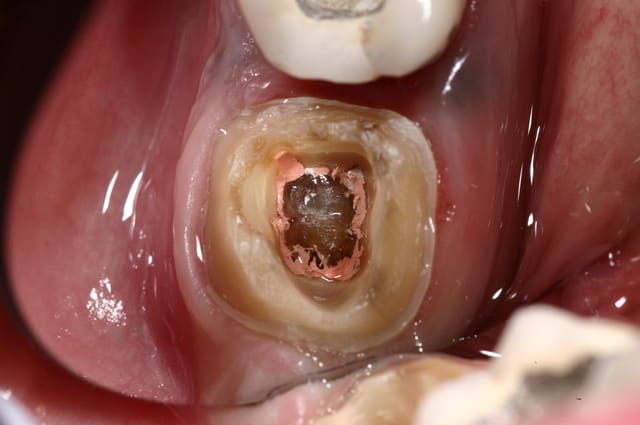

> Je ne vois pas quand un onlay n'est pas indiqué ?

> Même quand il ne reste rien, la preuve ci-dessous.

Dans ce cas de gros délabrement , tu privilégies la résine ou la céramique ?

@ Steph : Sur un délabrement tel que celui de la photo présentée, on peut envisager que la tendreté de l'onlay composite amortit et absorbe les forces et préserve ce qu'il reste de cette molaire alors que ce ne sera pas le cas avec l'onlay céramique.

je ferais plutot une V-prep en vitrocéramique Vita par exemple, c'est la plus souple et la plus facile à coller.

L'onlay répartit mieux les forces occlusales, et quand il s'agit d'onlay la céramique est recommandée.

Ici c'est de l'e-max.